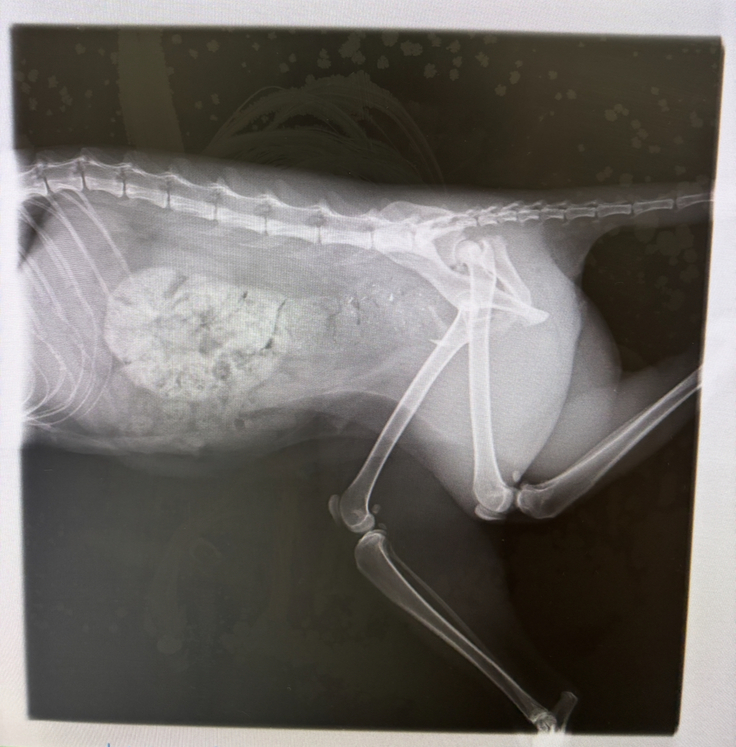

血液検査とレントゲン撮影してもらった結果、骨盤が粉砕骨折、右側は仙腸関節脱臼とのことでした。事態は思っていたよりも悪く、骨折により便の通り道が狭くなっていて排泄がうまくできず、腸が便でパンパンの状態でした。(下:画像の赤丸部分)そして、このままだと便を詰まらせて命に関わるとのことで手術を推奨されました。

左画像:術前 / 右画像:術後